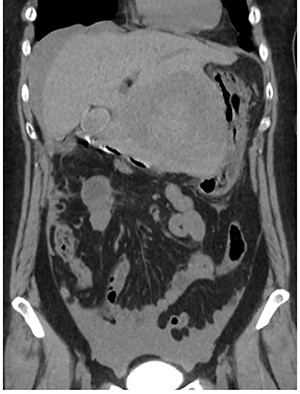

A 56-year-old woman presented to another hospital with acute abdomen. Computed tomography (CT) examination demonstrated a tumor 10 cm in diameter that protruded from the left lateral segment of the liver, with evidence suggestive of rupture of the liver tumor (Fig. 1). Since the patient was in good general condition, she was referred to our hospital for further evaluation. Her blood biochemical parameters when she was referred to our hospital were hemoglobin: 11.6 g/dl, albumin: 3.4 g/dl, γ-globulin: 18.5% and anti-acetylcholine receptor antibody: <0.3 nmol/L. Dynamic CT presented a liver tumor 10 cm in diameter, which was located at the left lateral segment of the liver, with a clear margin. A mass with an irregular margin was also identified in the anterior mediastinum (Fig. 2). On percutaneous angiography, since obvious extravasation of the contrast medium could not be identified, the arteries of the left lateral segment were embolized to prevent re-bleeding. Although a definitive preoperative diagnosis could not be made using magnetic resonance imaging (MRI) (Fig. 3), fluorodeoxyglucose positron emission tomography (FDG) showed increased FDG uptake in both the hepatic and anterior mediastinal tumors (Fig. 4). Although the liver tumor was suspected to be metastasis secondary to a thymoma based on the clinical findings, percutaneous tumor biopsy was performed to confirm the pathological diagnosis. The biopsy suggested malignant T-cell lymphoma or metastatic thymoma. In order to prevent re-rupture of the hepatic tumor, to confirm the pathological diagnosis and to potentially achieve a curative resection, the patient underwent laparoscopic left lateral segmentectomy (Fig. 5). Although the tumor was found to be adherent to the stomach, blunt dissection was possible. In addition, no peritoneal dissemination was detected. The surgical duration was 212 min and estimated blood loss was 50 ml. The liver tumor was pathologically diagnosed as metastatic thymoma type AB (Fig. 6). The patient’s postoperative course was uneventful and she subsequently underwent radical thymectomy 3 months after the liver resection. The thymic tumor was pathologically diagnosed as thymoma type B2. Currently, 30 months after thymectomy, she remains free from tumor recurrence.

Abdominal CT at the onset of symptoms suggestive of acute abdomen. A 10 cm diameter liver tumor was seen to protrude from the left lateral segment of the liver and high-density ascites was identified around the liver.